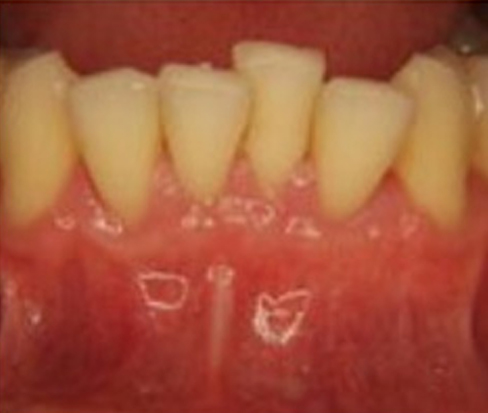

3. Scaling and Root Planing: If gum recession is caused by periodontal disease, Dr. Ghayoumi may recommend scaling and root planing. This deep cleaning procedure removes plaque and tartar from the tooth surfaces and smooths the root surfaces to promote gum reattachment and reduce inflammation.